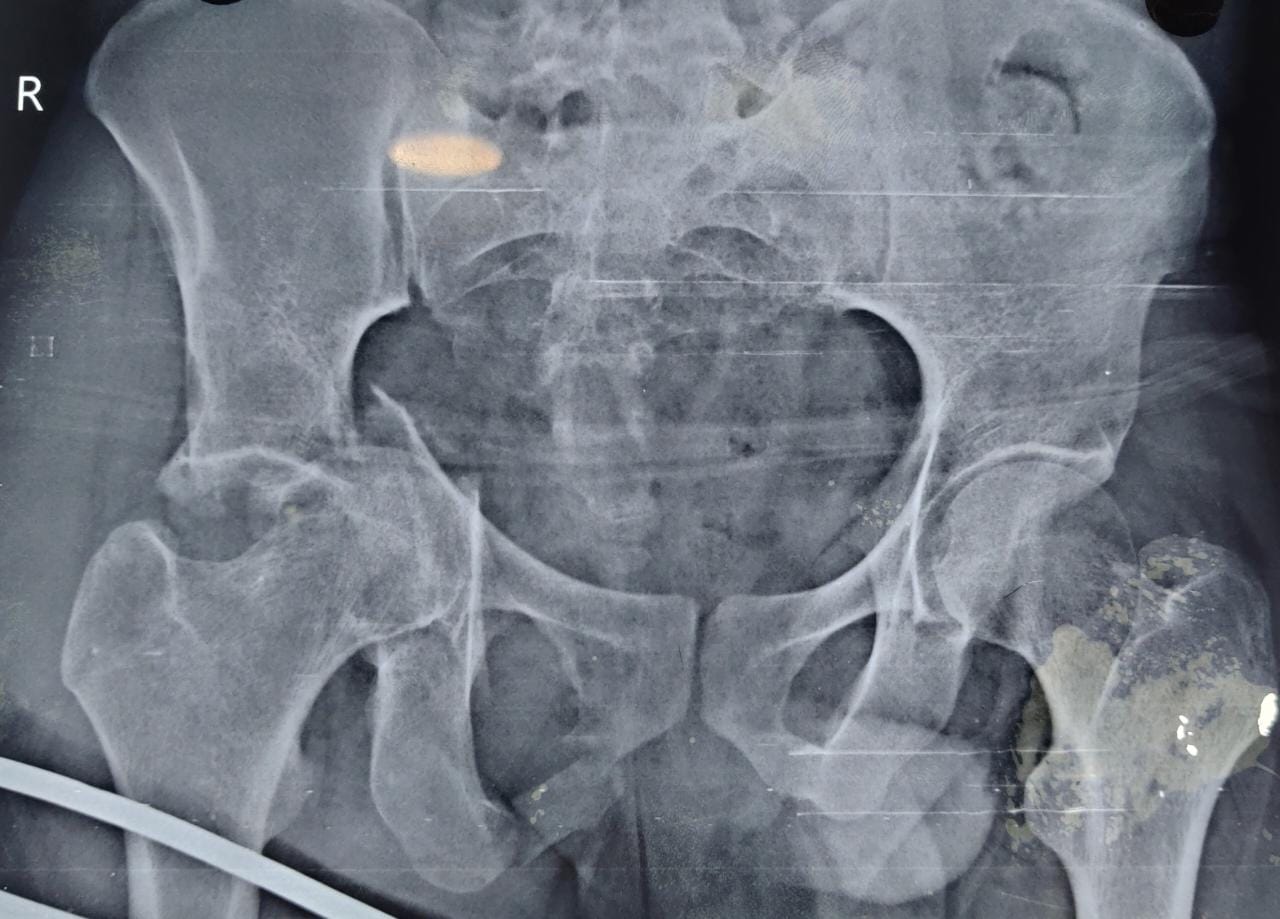

Pelvi Acetabular Trauma and Reconstruction

We as a tertiary care centre in the field of orthopaedics encounter a lot of complex trauma with extremely serious injuries around the hip

The injuries encompass hip dislocations with or without ACETABULAR fractures.

These fractures require urgent and precise surgical fixation to achieve the ultimate outcome. We at our centre routinely perform such surgeries.

If left untreated, these injuries can result in gait problems and may lead to painful restriction of movements. Hence to avoid these complications, we offer the expert and accurate advice coupled with definite treatment to deliver the best outcome.